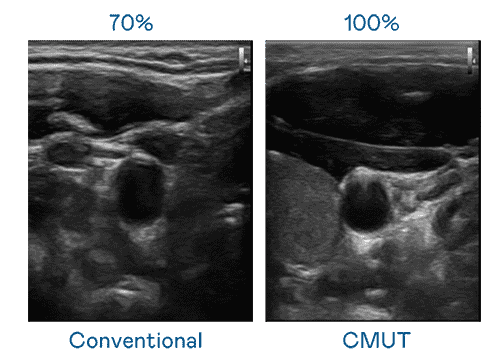

CMUT 技术是一种用电容式微机电元件来产生超音波讯号的技术。。。与传统 PZT 压电式技术相比,,,,CMUT 频宽增加 30%,,更宽频的超音波讯号让影像解析度大幅提升,,,是实现高影像品质医疗超音波扫描、、促进精准医疗发展的关键技术。。。。

超音波影像的解析度高低,,首先取决于探头能发出的讯号频宽。。。红龙扑克 CMUT 可提供高清晰的超音波讯号,,,,提供高频宽、、高灵敏度、、、、影像纹理细节更高的超音波影像,,协助医护人员缩短影像判读时间及利用精准的医疗影像进行诊断。。